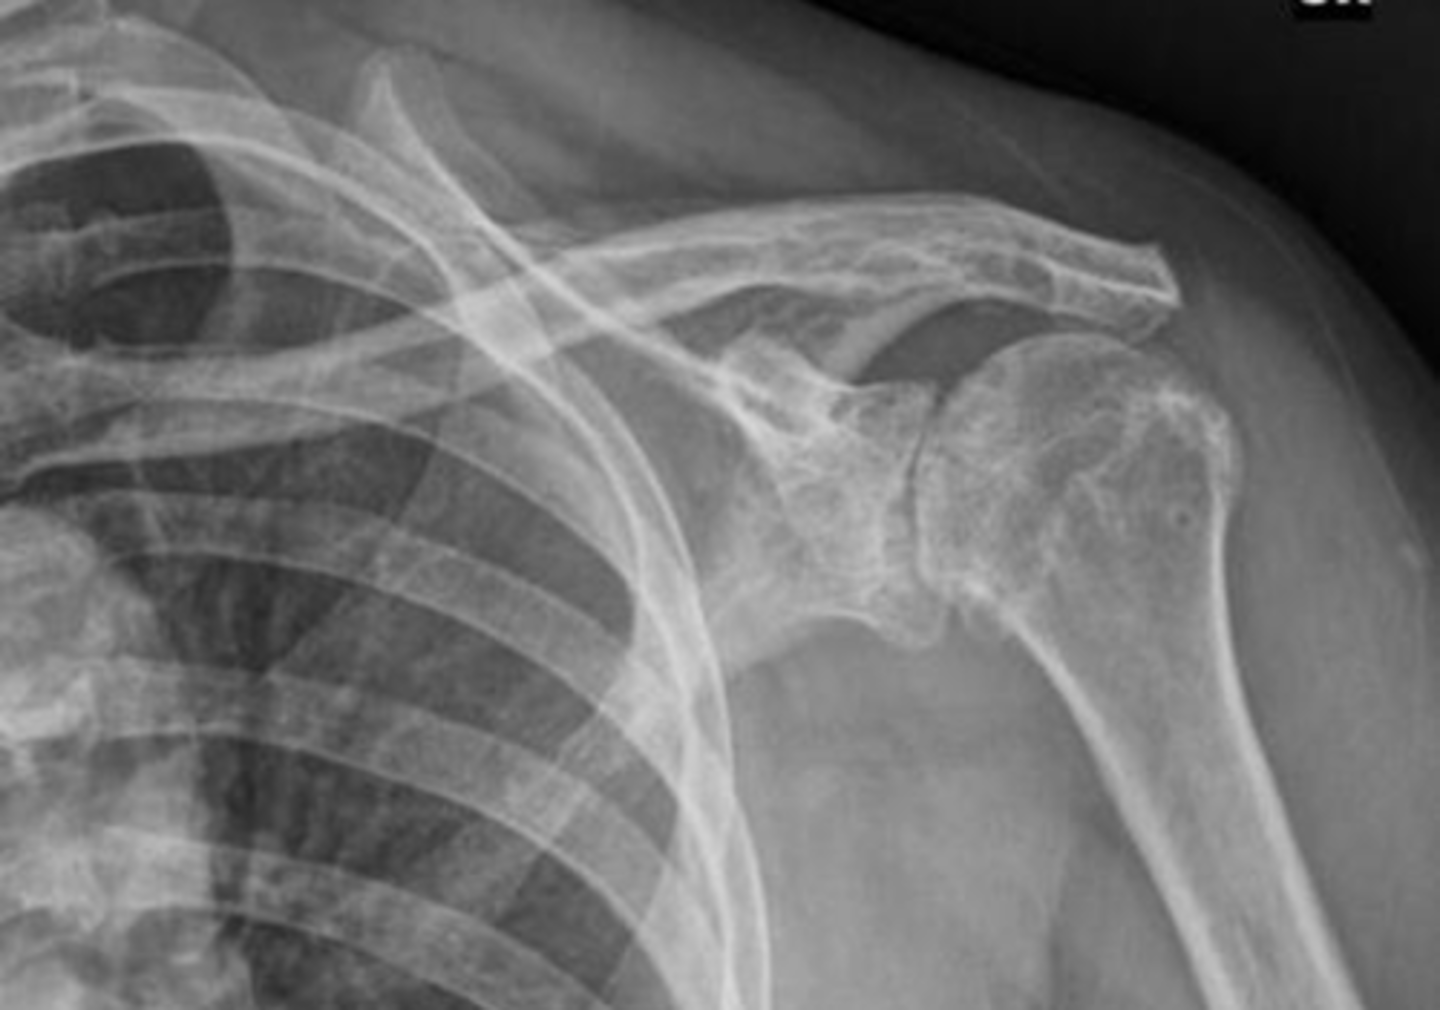

Condition: anterior GHJ dislocation

REALLY important to know BEFORE you relocate the humerus into the GHJ to know where the fracture(s) is and the integrity of the neurovascular structures

What is this image depicting? In an ideal scenario, determining this diagnosis is important before what? Why?

Condition: anterior GHJ dislocation via a Y-view -- makes dislocations MUCH more obvious

What is this image depicting? What view is it?